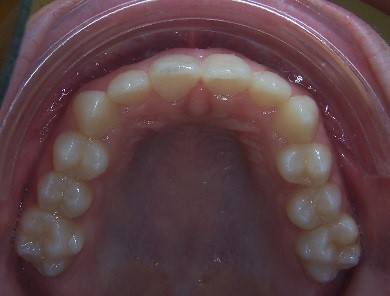

Key #2: An expander during the early mixed dentition allows the primary teeth to anchor the expansion appliance. This has significant benefits for permanent dentition that eliminate potential adverse effects, including dehiscence of the buccal bone, gingival recession, and root resorption. Expansion appliances use the strength of the roots and surrounding bone of the teeth to which they are attached. Consequently, those teeth and supporting bone carry the lateral pressure of the expansion as the suture opens. When primary teeth support the expander, the succedaneous bicuspids and canines do not bear any expansion pressure. The newly erupting teeth only benefit from the additional space development the expander has created. The acrylic bonded expander is easily constructed to adapt exclusively to the primary dentition, and has the added benefit of spreading the attachment over several teeth on each side. A banded hyrax appliance can be attached to the second primary molars and canines, or the permanent first and primary first molar. Studies have reported that using a Haas expansion appliance attached to the second primary molars and primary canines is successful and stable.

Key #4: When teeth erupt into a prepared site with adequate bone and soft tissue support, it is ideal for long-term stability and sound periodontal support. A similar protocol is followed when preparing a site with a graft for receiving an implant or grafting in an alveolar cleft site to receive the erupting canine. To prepare the space for expansion, follow the same principles for site preparation. In a crowded developing dentition, the plan to develop eruption space will decrease the risk of ectopic eruption with a compromised gingival attachment